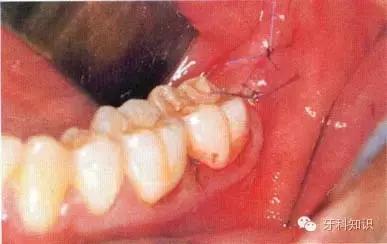

阻生牙拔除术:

临床分类

近中倾斜第三磨牙

手术的难易程度:A、B及C分类表示阻生牙的位置与第二磨牙的牙冠、牙颈部及牙根的关系。手术的难度随阻生深度的增加而增加。第Ⅰ、Ⅱ及第Ⅲ类阻生牙与第二磨牙和下颌升支之间的距离相对应